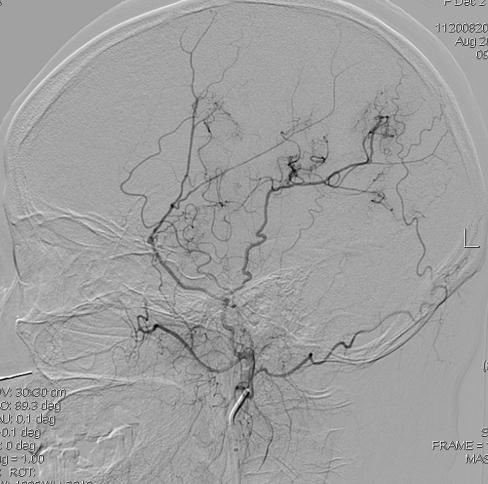

造影显示右侧大脑前明显变细,大脑中只有很少的分支:

左侧大脑中分支更少,虽然正位看还有一些分支,但是侧位看,大脑半球上外侧面大面积的区域没有血液供应,尤其功能区: